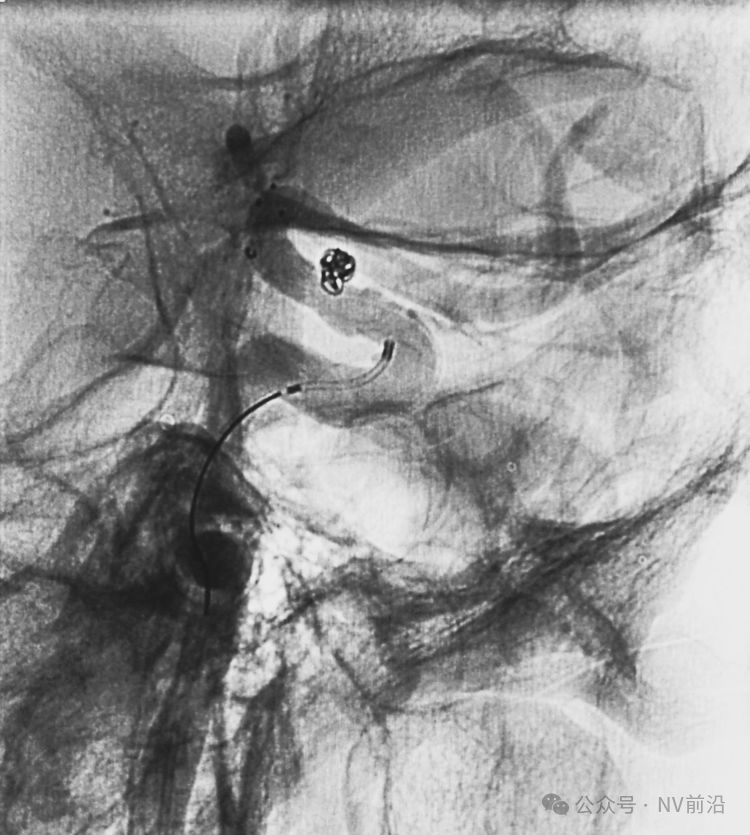

Solitaire 4×15支架(绿线)跨瘤颈半释放,压住微导管(红线)。

经微导管向瘤腔内送入首枚弹簧圈(QC-2-4-3D)。

继续送入两枚QC-1.5-2-Helix,完全栓塞动脉瘤,部分圈突入载瘤动脉。